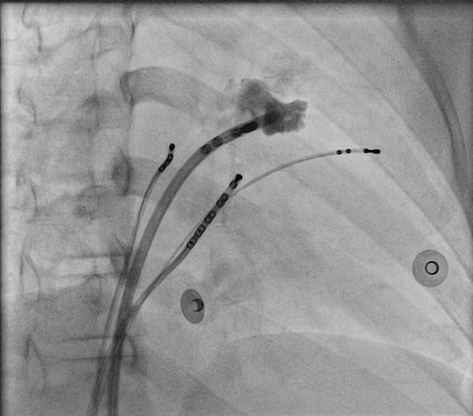

Stability

• Sheath

• Catheter course

• Retrograde approach

• Pacing if possible

• Entrain if during tachycardia